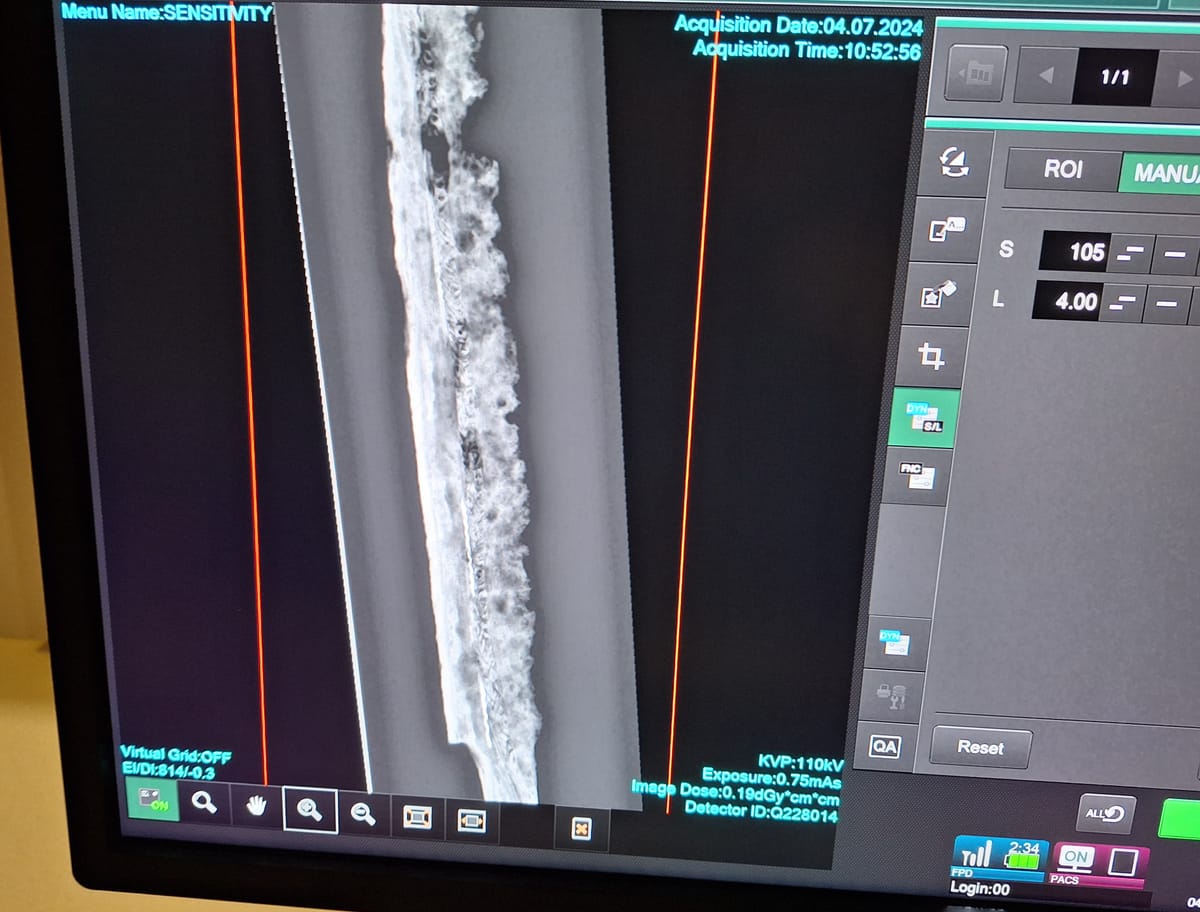

X-ray technology at the University of Suffolk is shedding new light on historical artefacts from Ipswich Museum, including a 200,000-year-old mammoth vertebra.

The big picture: The project involves using state-of-the-art radiography equipment to examine a variety of museum artefacts, from prehistoric remains to Anglo-Saxon weapons.

A mammoth vertebra from Ipswich may show signs of illness that affected the animal's final years.

An Anglo-Saxon fighting knife revealed an intricate pattern, suggesting it belonged to a high-status individual and X-rays of a taxidermied corncrake provided insights for future conservation efforts.